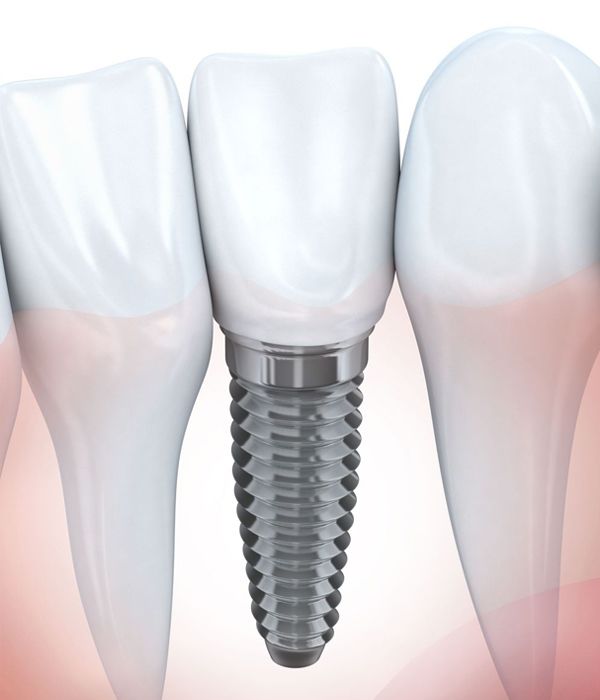

Dental Implants

Dr. Healy and Dr. Hurtado offer several types of implants including traditional and same-day implants, as well as the All-on-4® method. We are one of the few practices in New Mexico to use a state-of-the-art live navigation surgery system for more accurate implant placement.